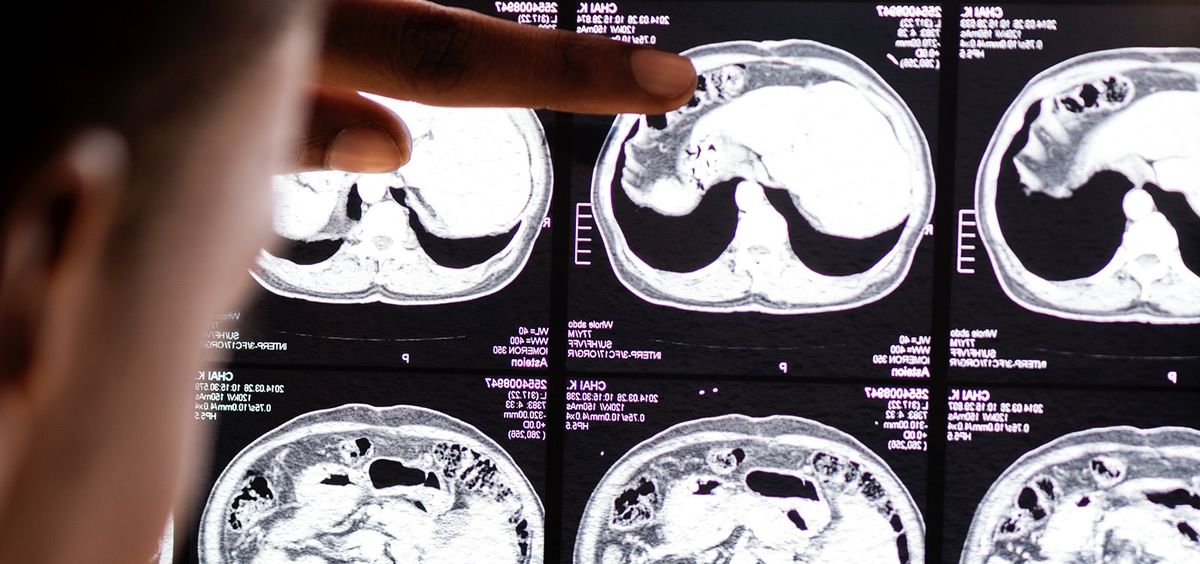

Los neurólogos desarrollan también investigación para lograr mejorar la prevención y el tratamiento del ictus. "Mediante ensayos clínicos, una vez desarrollados los tratamientos en el laboratorio y demostrar que también son efectivos en humanos. Se están investigando muchas técnicas de tratamiento y prevención. Una de las líneas más en boga son los tratamientos para mejorar la reparación cerebral. Sabemos que el cerebro tiene una capacidad de reparación endógena, una cierta plasticidad y cuando se produce un daño de este tipo se ponen en en marcha mecanismos propios de recuperación", afirma coordinadora del Grupo de Estudio de Enfermedades Cerebrovasculares de la SEN.

De hecho, tal y como apunta María Alonso de Leciñana, los principales estudios se centran en la utilización de células madre y otros componentes celulares, en busca de la plasticidad idónea para mejorar la capacidad de recuperación cerebral.